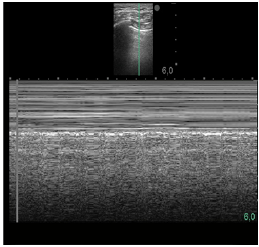

Um paciente de 50 anos de idade encontra-se, internado na UTI por conta de choque séptico de foco pulmonar, em ventilação mecânica na modalidade pressão e no modo assisto-controlado. Pela manhã foi submetido a acesso venoso central em veia axilar guiado por ultrassonografia. Ao exame físico, notou-se que o paciente está com hipotensão e taquicardia. A primeira hipótese diagnóstica é pneumotórax e é realizada radiografia com imagem apresentada.

Qual imagem abaixo corresponde ao achado ultrassonográfico para o paciente em questão?

De acordo com a imagem, a